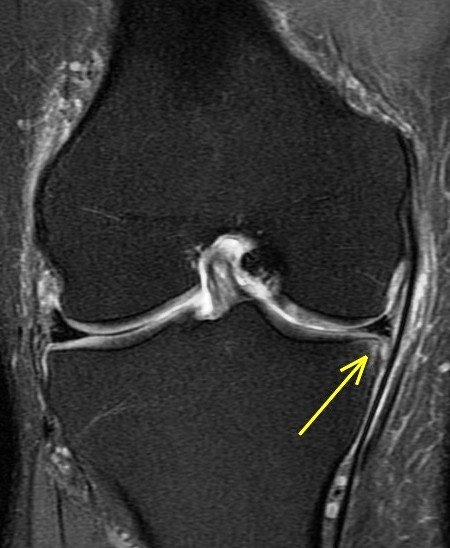

44 y/o male recreational runner. 2 week history of medial pain. r/o mmt.

Bone marrow edema is the radiologists friend. The posterior horn tear is easy to see. The displaced meniscus flap into the coronary recess adjacent to the body of the meniscus isnt so easy to see. The presence of bone marrow edema should alert us to the possibility of adjacent pathology leading to the reactive changes in the bone.

Unstable displaced medial meniscus tear( RID2772 ) with reactive tibial edema